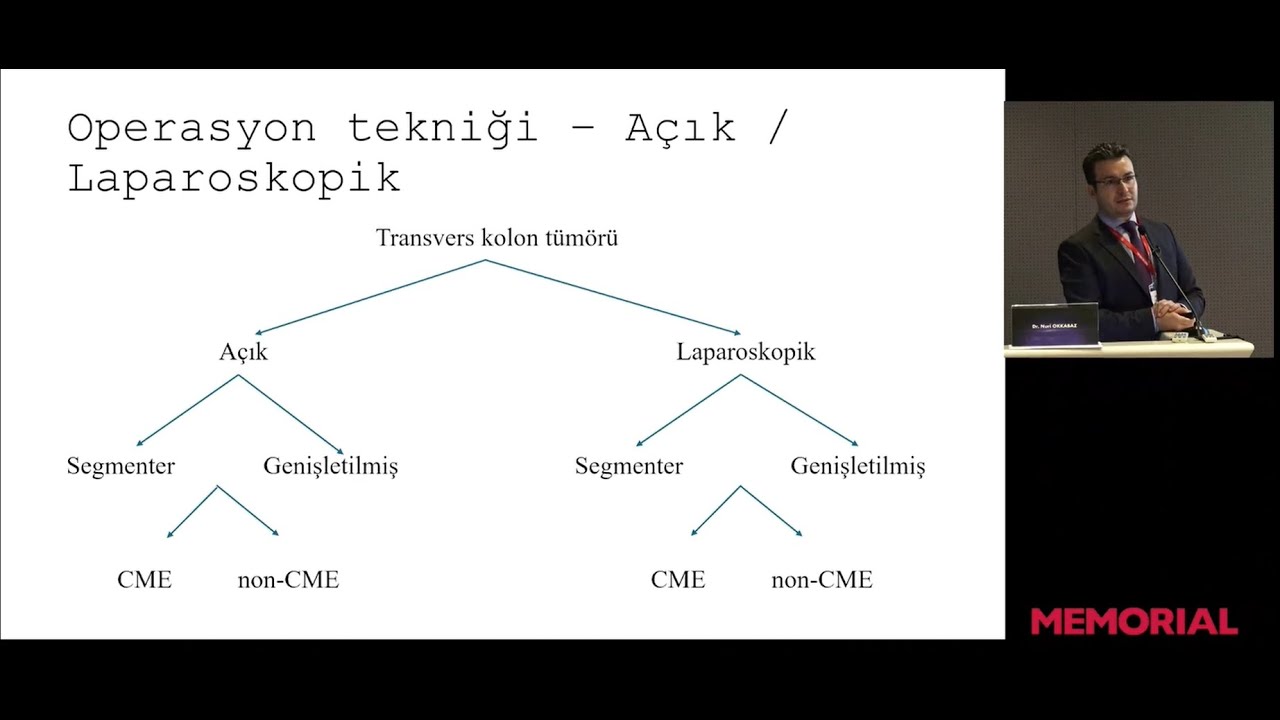

A conference presentation showcasing the technical details and surgical footage of transverse colon cancer surgery, which is often considered challenging by many surgeons and therefore frequently performed as an open procedure.

Approach to Colon Cancer